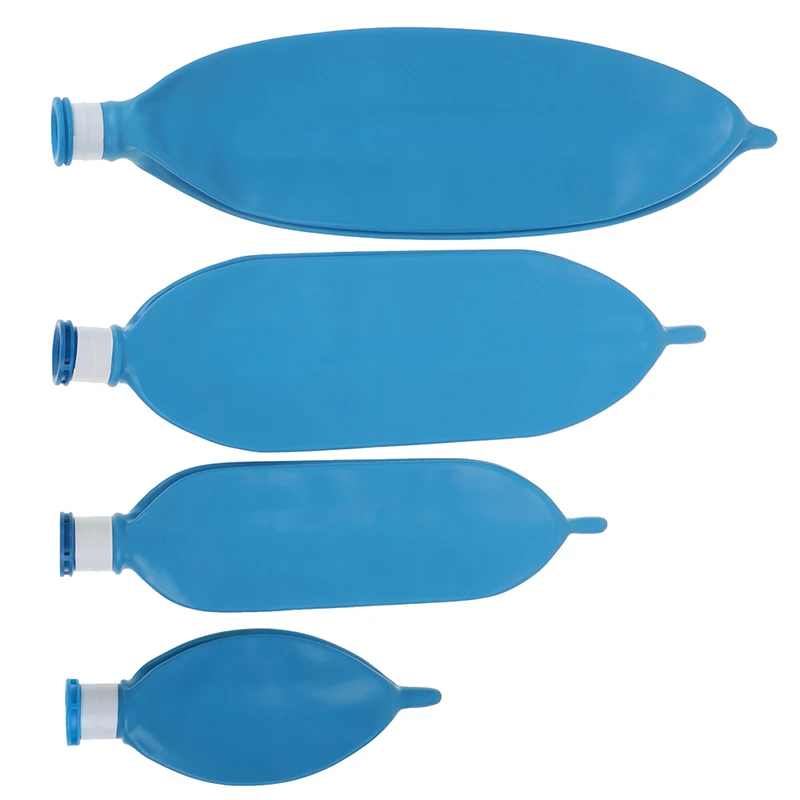

Латексный одноразовый дыхательный аппарат для анестезии объемом л, 1 л, 2 л, 3 л

Описание:Материал: латексРазмер: 0.5л 1Л 2л 3лЦвет: синий